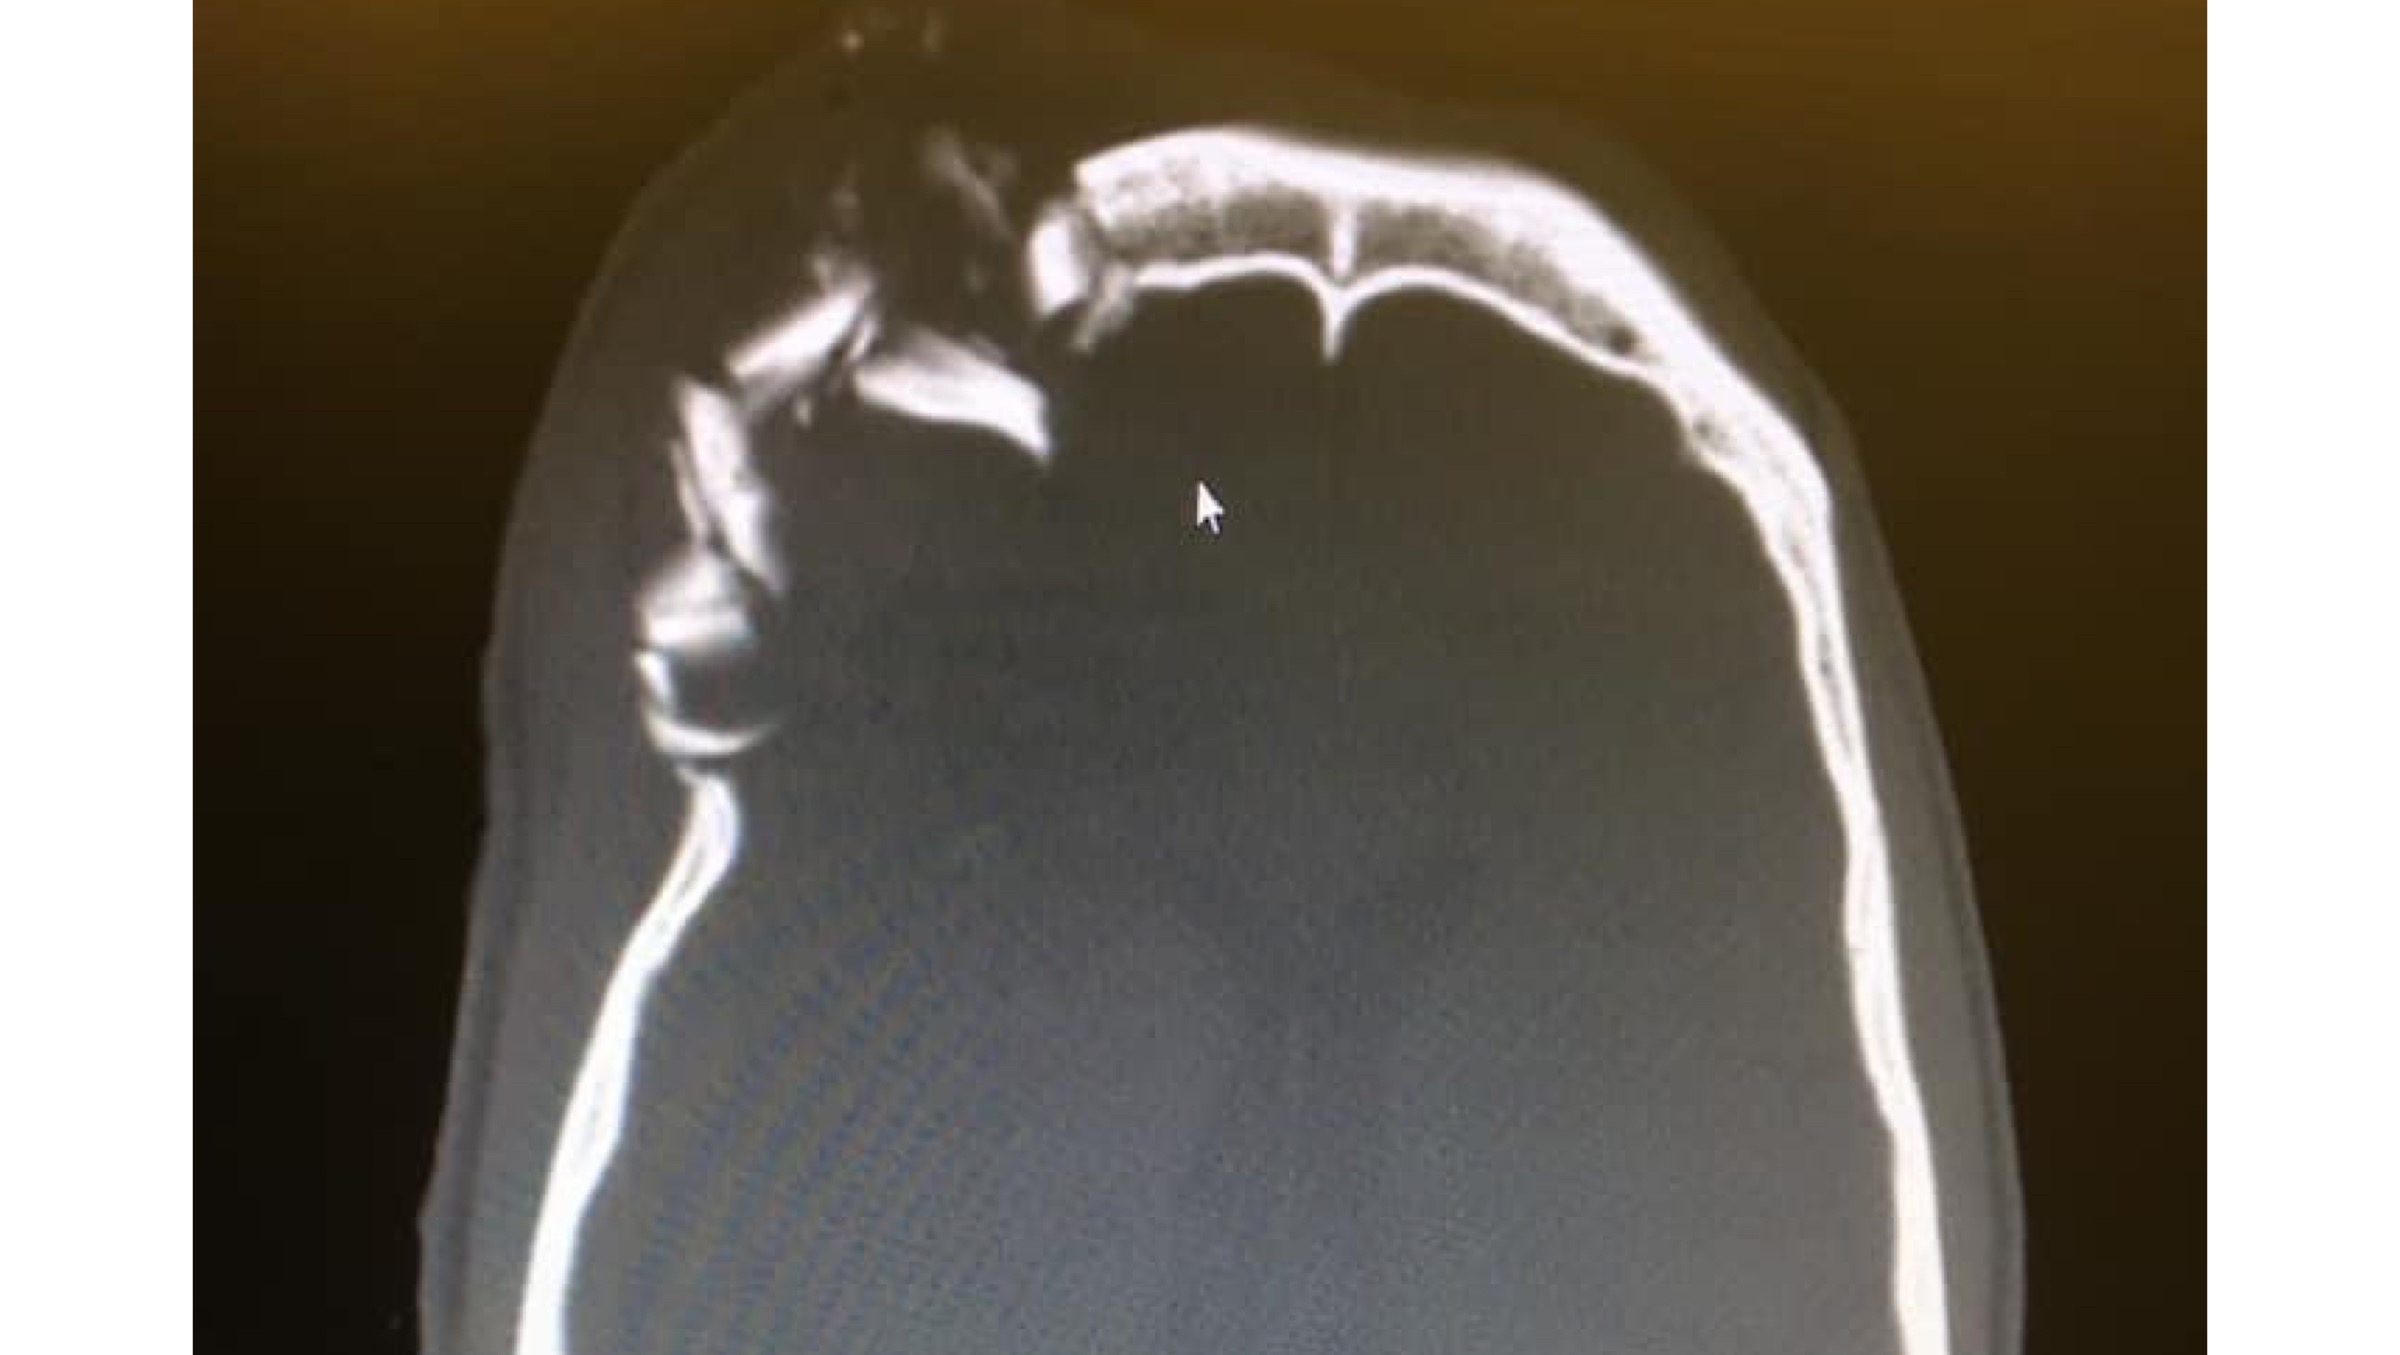

On June 16 Mash was helicopter rescued after being struck in the face by a softball size rock. He was airlifted to UC Davis Medical Center for emergency brain surgery that saved his life. After spending almost a month in the hospital he received a second surgery to rebuild his skull and orbital. He is currently waiting for a final surgery to remove his right eye.